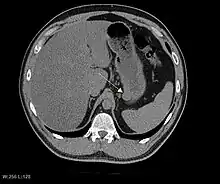

The purpose of radiologic imaging is to locate the lesion, evaluate for signs of invasion and detect metastasis. Features of GIST vary depending on tumor size and organ of origin. The diameter can range from a few millimeters to more than 30 cm. Larger tumors usually cause symptoms in contrast to those found incidentally which tend to be smaller and have better prognosis.[4][13] Large tumors tend to exhibit malignant behavior but small GISTs may also demonstrate clinically aggressive behavior.[14]

Barium fluoroscopic examinations and CT are commonly used to evaluate the patient with abdominal complaints. Barium swallow images show abnormalities in 80% of GIST cases.[14] However, some GISTs may be located entirely outside the lumen of the bowel and will not be appreciated with a barium swallow. Even in cases when the barium swallow is abnormal, an MRI or CT scan must follow since it is impossible to evaluate abdominal cavities and other abdominal organs with a barium swallow alone. In a CT scan, abnormalities may be seen in 87% of patients and it should be made with both oral and intravenous contrast.[14] Among imaging studies, MRI has the best tissue contrast, which aids in the identification of masses within the GI tract (intramural masses). Intravenous contrast material is needed to evaluate lesion vascularity.

Preferred imaging modalities in the evaluation of GISTs are CT and MRI,[16]: 20–21 and, in selected situations, endoscopic ultrasound. CT advantages include its ability to demonstrate evidence of nearby organ invasion, ascites, and metastases. The ability of an MRI to produce images in multiple planes is helpful in determining the bowel as the organ of origin (which is difficult when the tumor is very large), facilitating diagnosis.

As the tumor grows it may project outside the bowel (exophytic growth) and/or inside the bowel (intraluminal growth), but they most commonly grow exophytically such that the bulk of the tumor projects into the abdominal cavity. If the tumor outstrips its blood supply, it can necrose internally, creating a central fluid-filled cavity with bleeding and cavitations that can eventually ulcerate and communicate into the lumen of the bowel. In that case, barium swallow may show an air, air-fluid levels or oral contrast media accumulation within these areas.[14][17] Mucosal ulcerations may also be present. In contrast-enhanced CT images, large GISTs appear as heterogeneous masses due to areas of living tumor cells surrounding bleeding, necrosis or cysts, which is radiographically seen as a peripheral enhancement pattern with a low attenuation center.[13] In MRI studies, the degree of necrosis and bleeding affects the signal intensity pattern. Areas of bleeding within the tumor will vary its signal intensity depending on how long ago the bleeding occurred. The solid portions of the tumor are typically low signal intensity on T1-weighted images, are high signal intensity on T2-weighted images and enhanced after administration of gadolinium. Signal-intensity voids are present if there is gas within areas of necrotic tumor.[15][18][19]

Malignancy is characterized by local invasion and metastases, usually to the liver, omentum and peritoneum. However, cases of metastases to bone, pleura, lungs and retroperitoneum have been seen. In distinction to gastric adenocarcinoma or gastric/small bowel lymphoma, malignant lymphadenopathy (swollen lymph nodes) is uncommon (<10%) and thus imaging usually shows absence of lymph node enlargement.[13] If metastases are not present, other radiologic features suggesting malignancy include: size (>5 cm), heterogeneous enhancement after contrast administration, and ulcerations.[4][13][20] Also, overtly malignant behavior (in distinction to malignant potential of lesser degree) is less commonly seen in gastric tumors, with a ratio of behaviorally benign to overtly malignant of 3-5:1.[4] Even if radiographic malignant features are present, these findings may also represent other tumors and definitive diagnosis must be made immunochemically.